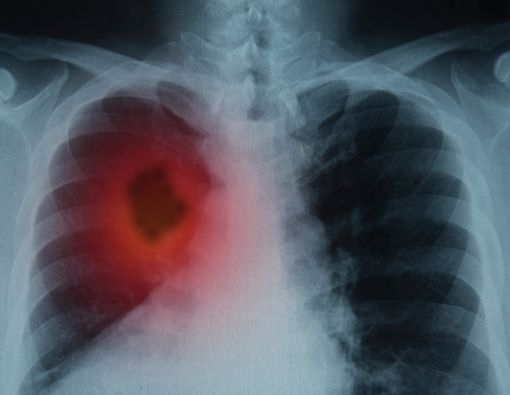

Tumor Paru, Massa Abnormal di Paru

Massa yang terjadi di paru disebut tumor paru. Ini merupakan hasil pembelahan sel yang tidak normal atau kematian sel dalam jaringan paru-paru. Jika pertumbuhannya berdiameter 3 sentimeter atau kurang, biasanya disebut nodul. Setiap pertumbuhan dengan diameter lebih dari 3 sentimeter disebut massa.

Tumor paru disebut jinak apabila tidak menyebar ke organ lainnya. Pertumbuhannya juga perlahan, dan bahkan berhenti tumbuh atau menyusut. Tumor seperti ini biasanya tidak mengancam jiwa.

Sementara itu, apabila Anda mengalami tumor paru dengan gejala yang berkebalikan dengan kondisi di atas, waspadalah. Bisa jadi, ada pertumbuhan tumor ganas atau kanker di paru-paru Anda. Gejala awal kanker paru adalah: